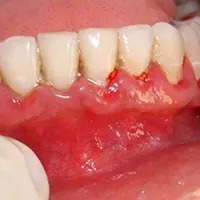

خونریزی لثه بعد از کامپوزیت

اگر شما هنگام مسواک زدن یا غذا خوردن دچار خونریزی لثه می شود با عفونت و ورم لثه مواجه شده اید. برای رفع این مشکل توصیه می شود به طور منظم و دائم از مسواک و نخ دندان استفاده کنید. در صورت جدی نگرفتن مسواک و نخ دندان پلاک ها در مکان اتصال لثه به دندان باقی خواهند ماند. این امر باعث ایجاد التهاب و عفونت لثه پس از کامپوزیت خواهد شد.

خونریزی لثه